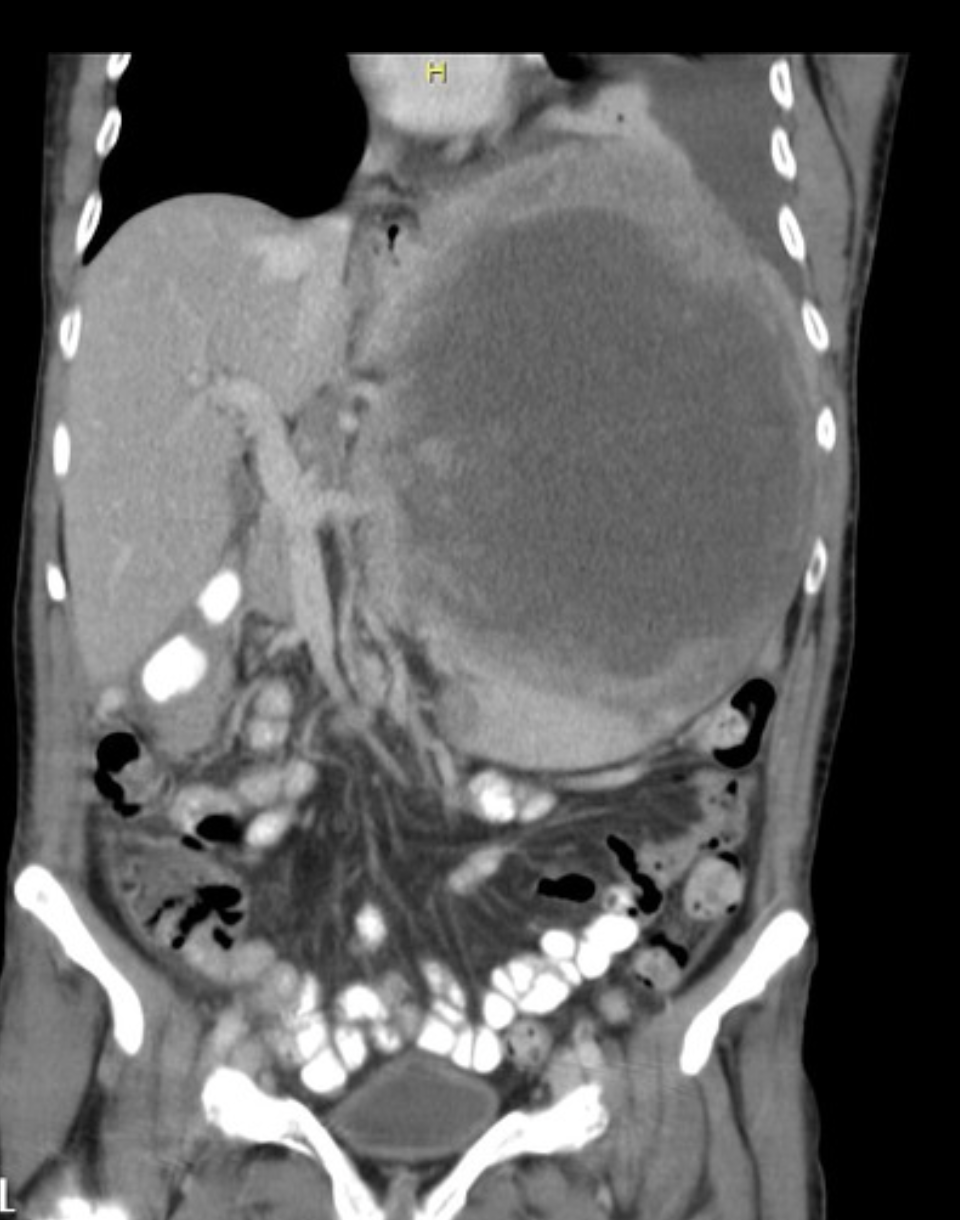

Pancreaticoblastoma

https://pubs.rsna.org/doi/10.1148/rg.264065012

Most common pancreatic tumour in children